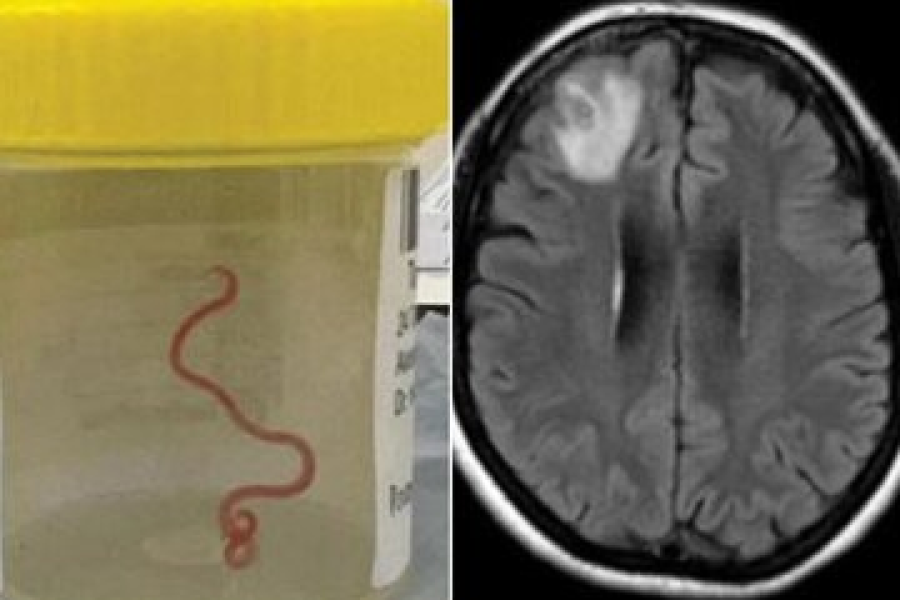

پزشکان در تصویربرداری MRI از مغز «لی» متوجه وجود جسمی خارجی در پشت چشم او شدند. آنها در بررسی بیشتر کرمی ۱۸ سانتیمتری سفید رنگ زندهای در مغز این مرد چینی دیدند که حرکت میکرد و سلامت او را به خطر انداخته بود. این کرم از نوع کرمهای نواری به نام اسپیرومترا بود. این نوع کرم معمولا در قورباغه، مار و پرندگان دیده میشود.

خوشبختانه پزشکان توانستند با جراحی مغز «لی»، او را از مرگ نجات داده و پس از ۱۰ روز بستری در بیمارستان مرخص کنند.